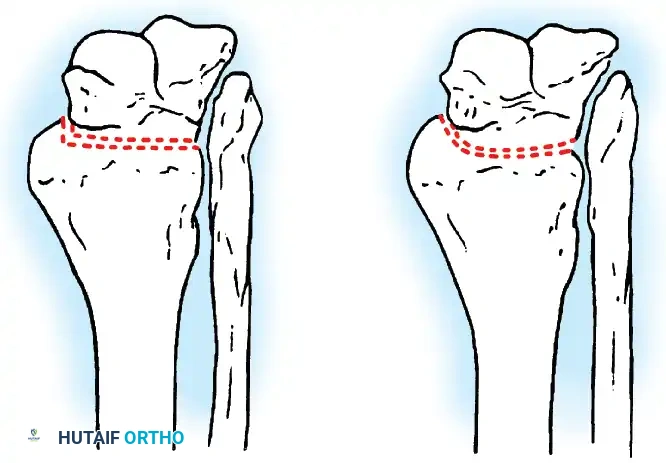

Transmalleolar (Transfibular) Approach

This approach utilizes a lateral incision over the distal fibula. A transfibular osteotomy is performed, reflecting the distal fibula distally or excising it entirely to be used as autograft. This provides unparalleled exposure of the lateral half of the joint and the posterior facet. It is highly effective for correcting severe varus/valgus deformities. A supplementary medial incision (medial malleolar osteotomy) can be added for complete joint exposure.

- Contour Preservation (Fishscaling): The remaining articular cartilage is meticulously denuded using curettes, and the subchondral bone is "fishscaled" or aggressively petalled with a sharp osteotome. This preserves the native ball-and-socket contour of the ankle, maximizing inherent bony stability and minimizing limb shortening.

- Planar Resection (Parallel Cuts): Two parallel cuts are made—one through the distal tibial plafond and one through the talar dome—using an oscillating saw. This technique resects a minimal amount of bone but creates perfectly flat, highly vascular cancellous surfaces that allow for excellent apposition and easy posterior translation of the talus. Extramedullary alignment guides (often repurposed from total knee arthroplasty systems) can be utilized to ensure precise, parallel resections.